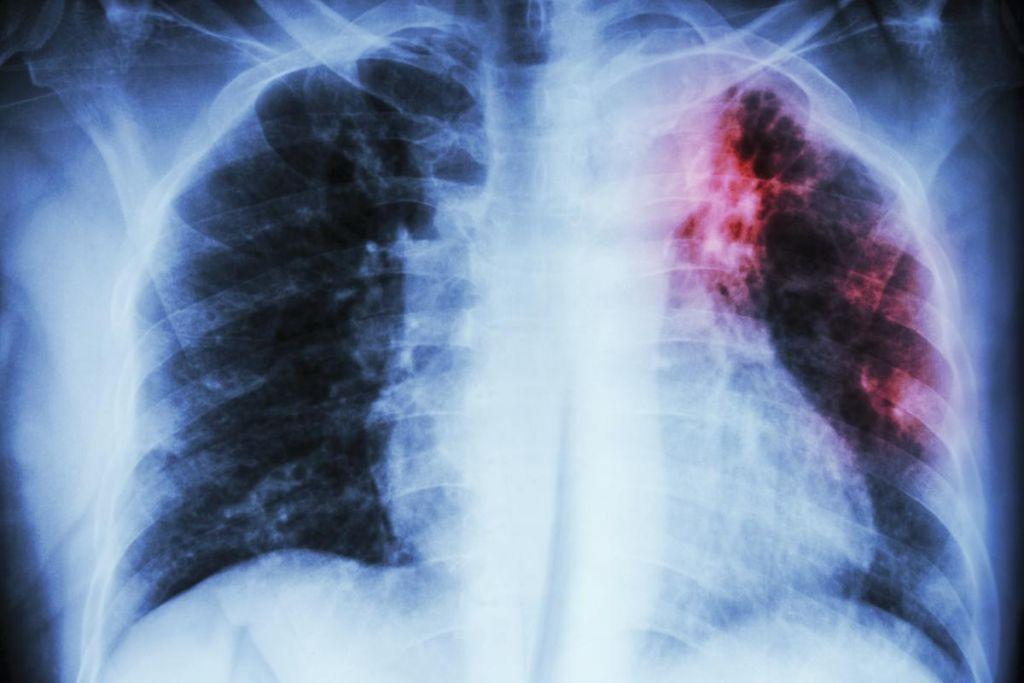

Η ιδιοπαθής πνευμονική ίνωση, που έχει μέση επιβίωση δύο έως πέντε χρόνια μετά τη διάγνωση, είναι μια πάθηση για την οποία χρειάζεται επειγόντως η ανάπτυξη καινοτόμων φαρμάκων, καθώς δεν έχει βρεθεί μέχρι σήμερα αποτελεσματική φαρμακευτική αντιμετώπιση.

Οι ερευνητές του ΕΚΠΑ και του Ερευνητικού Κέντρου Βιοϊατρικών Επιστημών «Αλέξανδρος Φλέμινγκ», που έκαναν σχετική δημοσίευση στο επιστημονικό έντυπο Journal of Medicinal Chemistry, παρουσίασαν έναν αναστολέα, που έδωσε πολύ ενθαρρυντικά αποτελέσματα σε πειραματόζωα με πνευμονική ίνωση, αντιμετωπίζοντας τη φλεγμονή και επαναφέροντας σε φυσιολογικά επίπεδα διάφορους δείκτες, όπως τη συγκέντρωση του κολλαγόνου στον πνεύμονα.